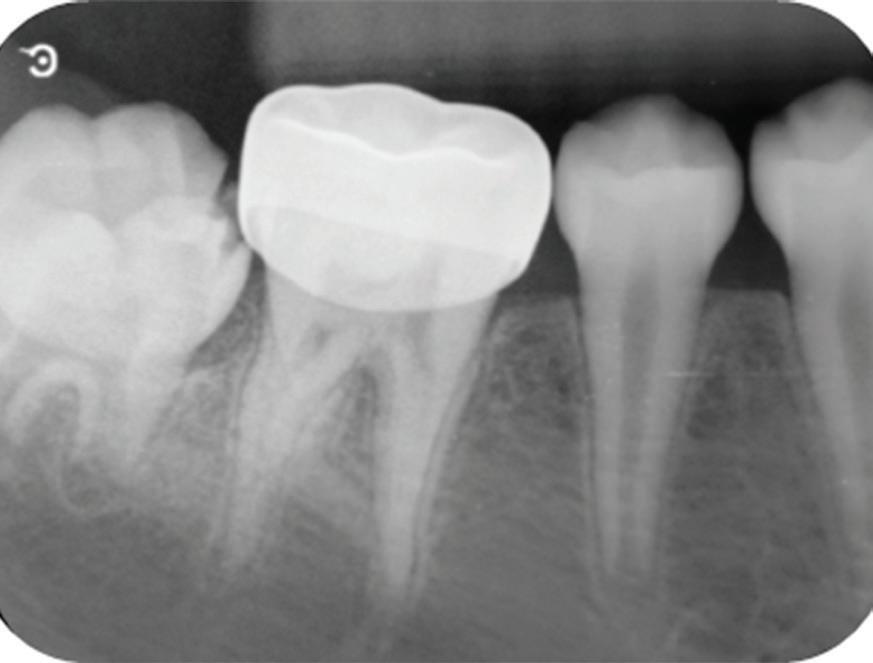

Approximately 15 months after SSC placement (49 months after PP), the patient returned with a complaint of sensitivity to cold stimuli in the treated tooth. Cold testing elicited sharp pain lasting approximately 10 seconds, but the results of the electric pulp test and percussion test were negative. Radiographic examination of the first molar showed a periapical radiolucency with a periapical index score of 3 (Fig 8).9 The tooth was diagnosed with irreversible pulpitis and asymptomatic apical periodontitis.

Radiograph 15 months after stainless steel crown placement, showing periapical radiolucency that indicates vital pulp therapy failure 49 months after partial pulpotomy.

Fig 8.